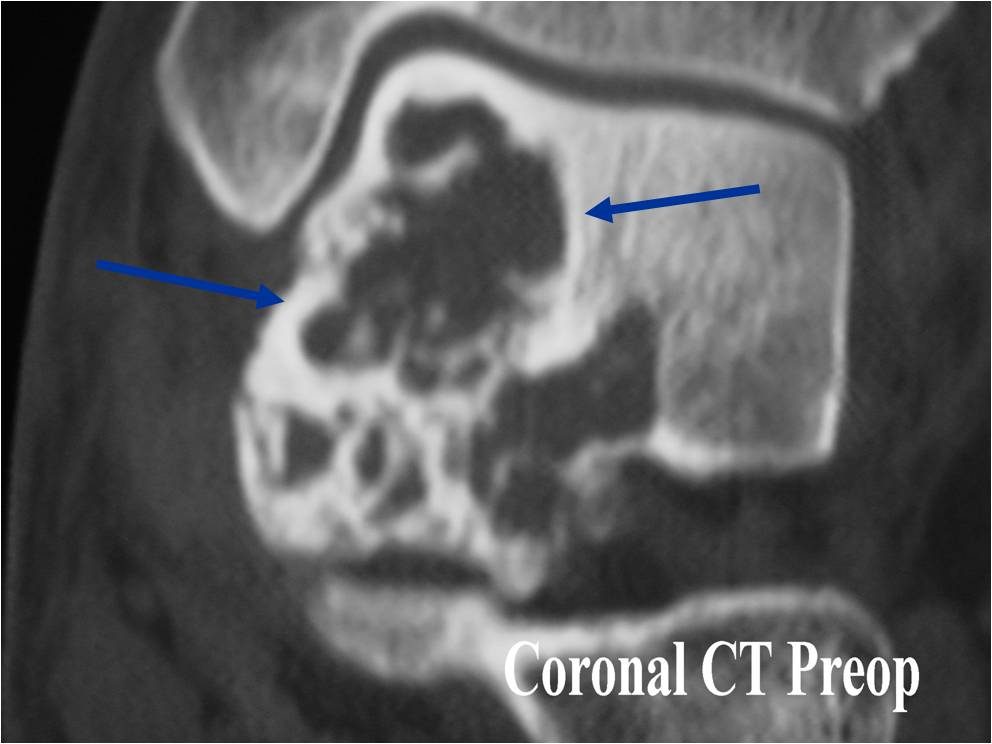

CT appearance:

- Most useful for detecting subtle mineralization not apparent on X-rays

- Useful for identifying intact periosteum around any expansile soft tissue component

- surrounding thin reactive shell of bone/mineralization (Egg Shell Rim of Calcification)

- helps place the tumor in a benign category

- helps evaluate:

- bony quality

- extent of bone and cortical destruction

- whether the subchondral plate of bone adjacent to the articular cartilage has been destroyed or is intact